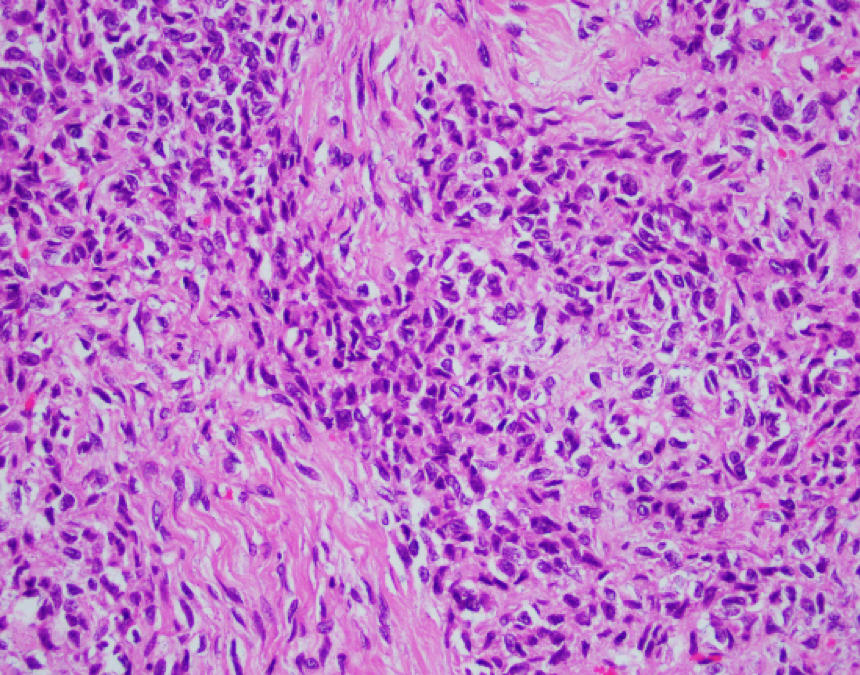

Patient is a 68-year-old female with a about 20 cm ovary mass. The mass has a mixed (solid/cystic) cut surface.

This is an adult granulosa cell tumor with areas of edema, necrosis, and calcification. A reticulin stain reveals diminished fibers, encompassing groups of tumor cells. Tumor cells are positive for SF-1 and inhibin, rare cells positive for calretinin, and negative for EMA, and CK7. The morphologic features, special stains, and immunophenotype are those of an adult-type granulosa cell tumor. Small cell carcinoma often has a much high mitotic figure rate, lack of cytological features of AGCT, and inhibin-. AGCT may be occasionally difficult to distinguish from fibromas or fibrosarcomas. Reticulum stains often show abundant intercellular fibrils in these tumors.